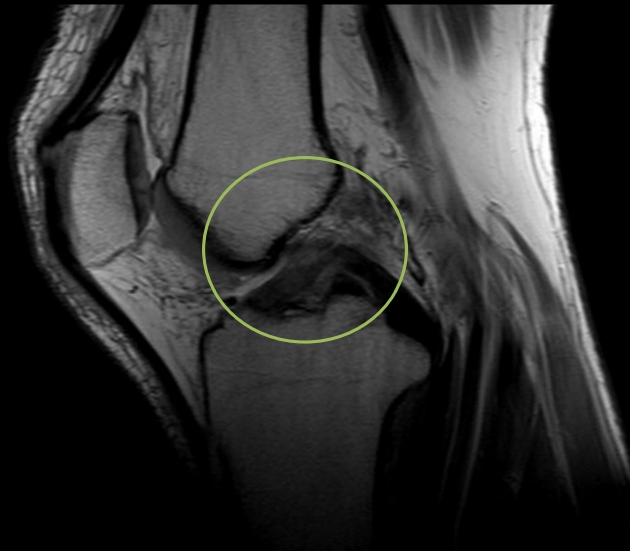

圖:36歲籃球好手李先生術前